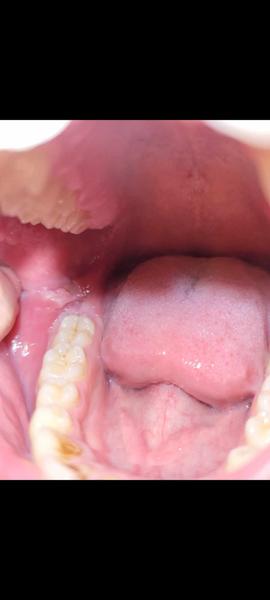

Čo spôsobuje opuch na líci vľavo?

@lilyianka Ked si to z prstom trošku pohnem tak vnutri to je ako keby otvorene na 2 polovice , neviem to lepšie vysvetlit ..... celkom sa bojim

Mas poskodenu sliznicu a dostali sa ti tam bakterie z ust, tak sa ti to zapalilo. Nieco ako afta.

Mne to príde ako keď si zakusneš zubami do líca.